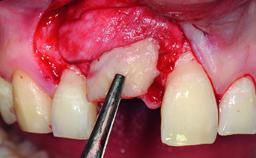

A 32-year-old female Caucasian patient with a compromised maxillary right central incisor was referred to us by a general dentist. Her chief complaints were discomfort and mobility of tooth 11 with unsatisfactory esthetics due to discoloration. The patient reported a previous trauma, some years earlier, as the origin of pathology on the afflicted tooth. Anamnesis was negative for any other dental or periodontal pathology in the remaining dentition. The patient did not take any medication and reported to be a light smoker (5–10 cigs/day). She had high esthetic expectations of her treatment. The extraoral examination revealed a high smile line with full exposure of her maxillary teeth and surrounding soft tissue in the area between the second premolars.

Bone Augmentation Horizontal|Simultaneous|Staged

Augmentation Materials Autogenous chips|Xenogenous|Membrane